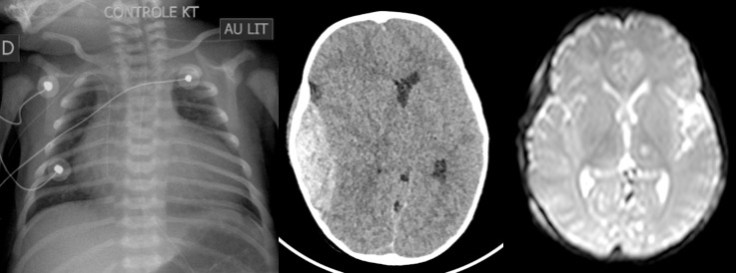

l’association de l’HED à une pathologie cardiaque ou respiratoire peut entrainer une ischémie cérébrale sévère, en raison de l’absence de réserve hémodynamique pour faire face à l’HTIC.